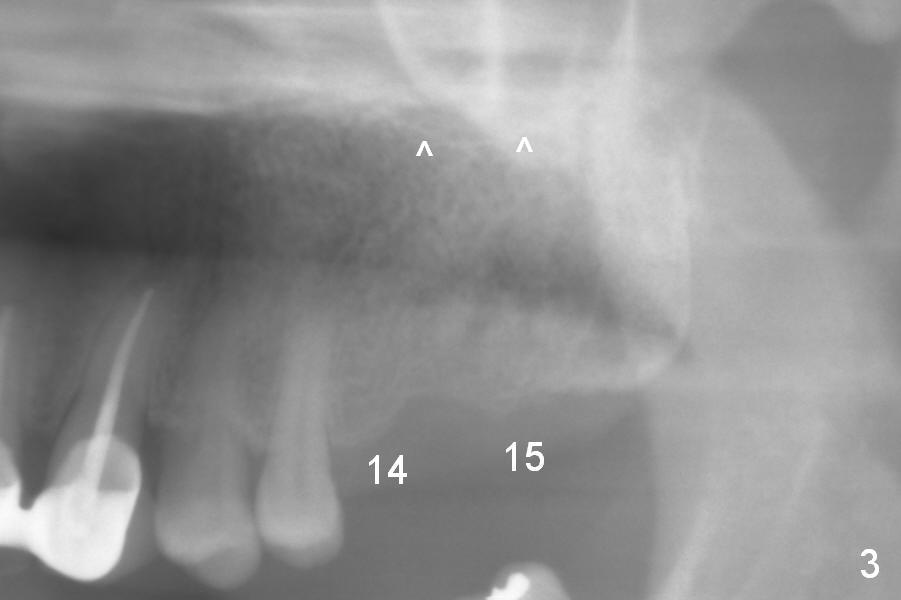

A 52-year-old man has multiple missing teeth. Since he has a lower partial denture (Fig.5), implants will be placed at the sites of #14 and 15 first (Fig.1). The site of #14 may need bone expansion if bone density is low, whereas the ridge at #15 is wide (Fig.2). There is no problem in height at the sites of #14 and 15 (Fig.3).

CBCT confirms that the ridge at #14 is narrower than that at #15. In contrast, the bone density is lower at #15 than that at #14 (Fig.7-9). If the keratinized tissue is wide, use 4 mm tissue punch (3 mm from #13). If incision is made, wheel saws will be used to split the ridge. Or use Magic split and osteotomes. Bone expanders are going to be used for bone expansion at #14 and bone condensation at #15 (Fig.8,9). Be careful while using bone expanders at #14, since the bone density is higher. There is a chance of plate fracture. Use drills if indicated. Fabricate splinted provisional after placement of abutments.